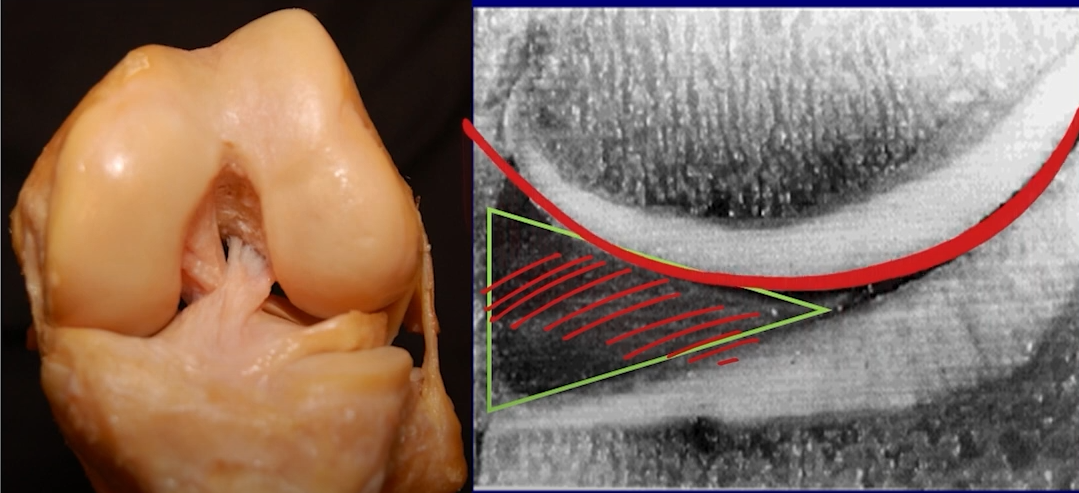

이러한 섬유 조질인 반월연골판은, 나이가 들면 들 수록 탄력이 떨어지게 되고 기능을 잃게 됩니다. 쉽게 생각하면 자동차 타이어를 3~4년 사용하면 타이어가 마모되는 원리와 같습니다.

일반 환자분들이 쉽게 찢어지게 되는 상황은 과도하게 굴곡되는 자세 입니다. 의자에 앉은 정도의 굽힘은 문제가 되지 않으나 그 이상의 굽힘이 있는 경우 반월연골판이 후방으로 전위되면서 찝히는 형태의 모습이 되게 됩니다. 이러면서 반월판은 손상을 받기 쉽습니다. 따라서, 농사일을 하거나 좌식생활을 하는 한국 노인층에서는 대부분 반월판이 파열되어 있는 경우가 많습니다.

이러한 퇴행성 원인 외에도, 회전력이나 강한 충격량으로 (운동선수) 찢어지기 쉽습니다. 다른 조직들과 달리, 회복이 어려운 편이며 찢어짐과 동시에 관절운동에 방해가 되기 시작하면 무릎이 걸리는 느낌 혹은 통증까지 나타날 수 있습니다.

아래와 같이 다양한 형태로 찢어질 수 있으며, 치료를 하지 않고 방치하는 경우 상당히 진행할 수 있습니다.